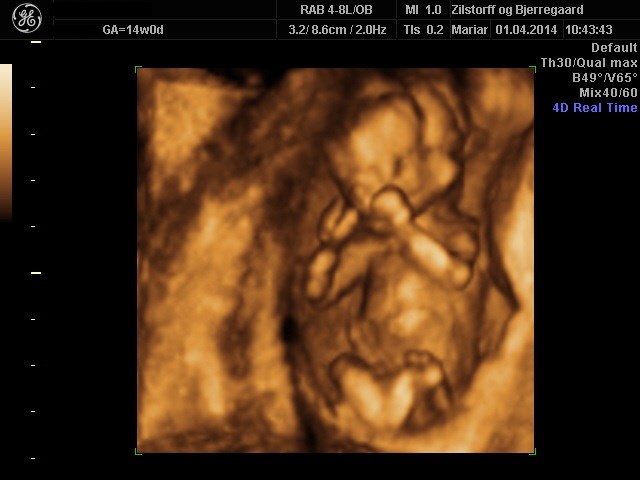

Du tænker måske på MD? Vi har selv betalt for denne skanning og man kan se kønnet allerede fra 14+0.

Der var ingen tvivl om at det var en lille pige. Ingen tissemand i sigte